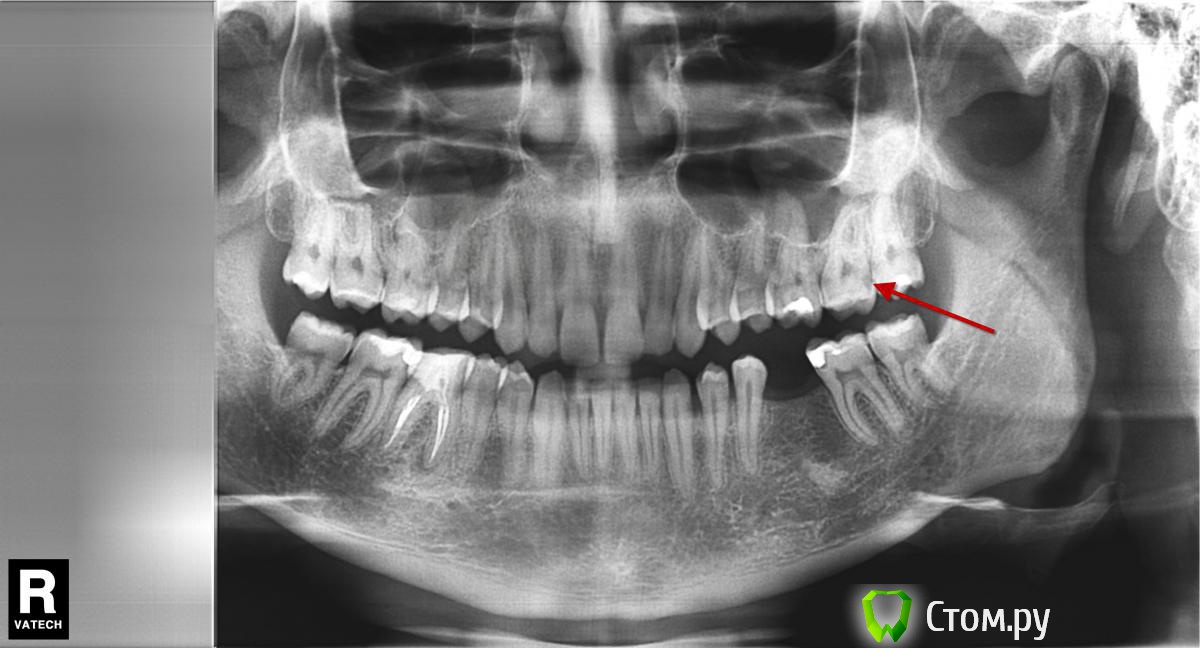

bobrdobr Опубликовано 5 февраля, 2014 Поделиться Опубликовано 5 февраля, 2014 Добрый вечер, Для планирования имплантации сделал панорамный снимок. Появилось несколько вопросов по терапии. В области 1 - это периодонтит? Зуб не беспокоит, был депульпирован и запломбирован два года назад. Нужно ли срочно перелечивать канал? В областях 2 и 3 темные кромки между пломбой и зубом могут быть кариесом? Понимаю, что панорамный снимок - не лучший способ диагностики. Заранее спасибо! Ссылка на комментарий

DmitrySH Опубликовано 6 февраля, 2014 Поделиться Опубликовано 6 февраля, 2014 Добрый вечер,1 - да, нужно. Хотя по снимку запломбировано нормально. 2 - возможно, но нужен визуальный осмотр Ссылка на комментарий

bobrdobr Опубликовано 21 февраля, 2014 Автор Поделиться Опубликовано 21 февраля, 2014 Спасибо всем за комментарии. Сегодня был у терапевта, все подтвердилось. 1. Полость на 27 зубе оказалась кариесом2. В областях 2 и 3 на снимке кариес Ссылка на комментарий